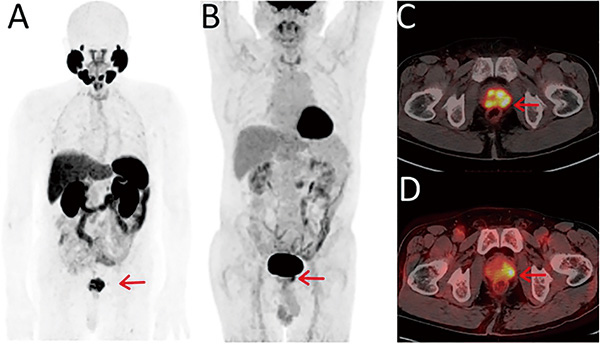

加拿大艾伯塔大学Mookerji等报告,利用前列腺特异性膜抗原(PSMA),在前列腺癌的局部区域分期方面,氟-18 PSMA-1007正电子发射断层扫描/计算机断层扫描(18F-PSMA-1007 PET/CT)优于多参数磁共振成像(MRI)。该结果支持PSMA PET在中危和高危肿瘤的术前应用。(JAMA Oncol. 2024年7月1日在线版)

PSMA在前列腺癌中过度表达,并与肿瘤侵袭性相关。根据目前的研究,PSMA PET在前列腺癌的转移分期方面优于常规成像,但是关于第二代PSMA PET放射性配体在局部区域分期中应用的研究有限。为了比较18F-PSMA-1007 PET/CT和多参数MRI在中危和高危前列腺癌区域分期中的准确性,该项Ⅱ期前瞻性验证配对队列研究于2022年3月至2023年6月在加拿大2家三级医院纳入接受了所有影像学检查和根治性前列腺切除术的患者,以评估两项技术的准确性,并以组织病理学检查结果作为参考标准。

结果显示,在150例符合条件的前列腺癌患者中,134例最终接受了根治性前列腺切除术(手术时的平均年龄为62.0岁±5.7岁)。在准确判别最终的病理肿瘤分期中,PSMA PET优于MRI(45% vs. 28%,P=0.003);在对重点关注淋巴结(94% vs. 83%,P=0.01)、偏侧性(64% vs. 44%,P=0.001)和囊外侵犯(75% vs. 63%,P=0.01)的准确判别方面,PSMA PET均优于MRI,但在精囊侵犯(91% vs. 85%,P=0.07)方面则不及。 (编译 段晶耀)